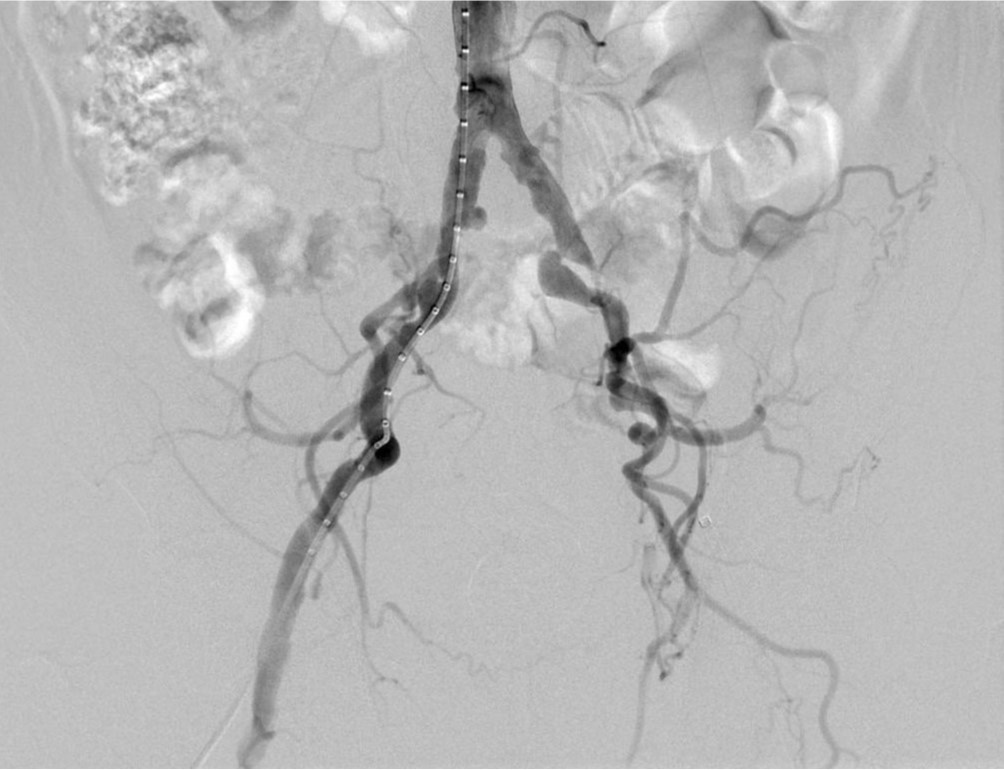

양쪽 총장골동맥을 천자하여 우측 총대퇴동맥을 통해 시행한 혈관조영술에서 좌측 바깥장골동맥과 근위부 좌측 총대퇴동맥의 완전폐색이 관찰됨(Fig. 1).

Fig. 1.

Fig 1. Pelvic angiography shows chronic total occlusion of left EIA and left proximal CFA.